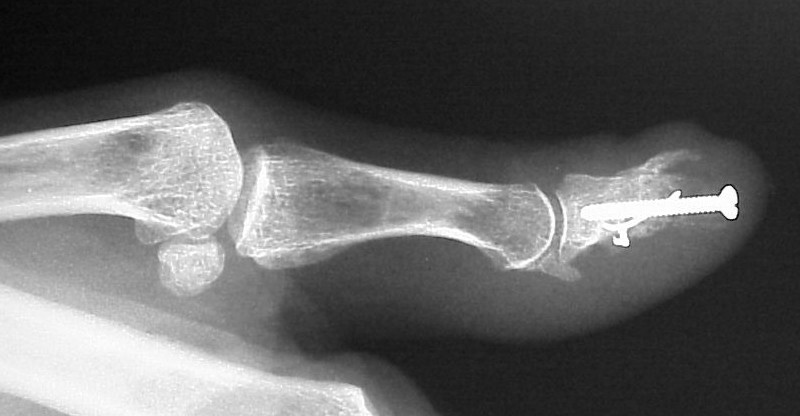

Exploration revealed no discrete  tumor, and a nondiagnostic frozen section. Because of diagnostic uncertainty and in order to avoid intraoperative cross contamination, a cancellous freeze dried allograft was used as a terminal graft:

This incorporated, with some terminal resorption: